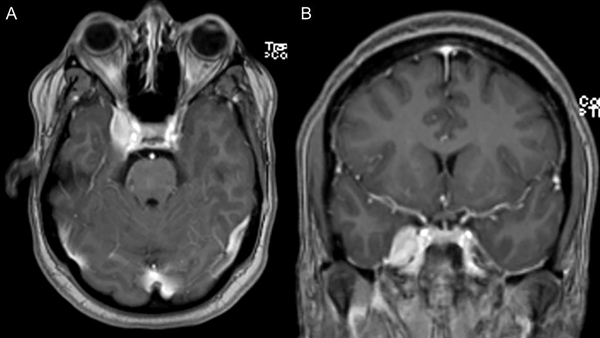

Paciente de 44 años, sin antecedentes de relevancia, que consultó por cuadro de dolor facial intenso, de tipo urente en territorio V1, V2 y V3 lado derecho. Se realizó Resonancia Magnética Nuclear (RMN) de cerebro en la que se observó lesión nodular extraaxial, con base de implantación en cara lateral del seno cavernoso derecho con intenso realce postcontraste; compatible en primera instancia con un meningioma con extensión a fosa temporal y cavum de Meckel (Figura 1). Realizó tratamiento farmacológico con Carbamazepina a dosis máxima y Gabapentin, sin mejoría de los síntomas. Posteriormente intercurrió con farmacodermia secundaria.

Figura 1. RMN de cerebro en secuencia T1 con contraste (preoperatoria) corte axial y coronal (A y B) que revela una lesión de masa bien delimitada que afecta al seno cavernoso y cávum trigeminal del lado derecho, que realza fuertemente a la administración de contraste con gadolinio.